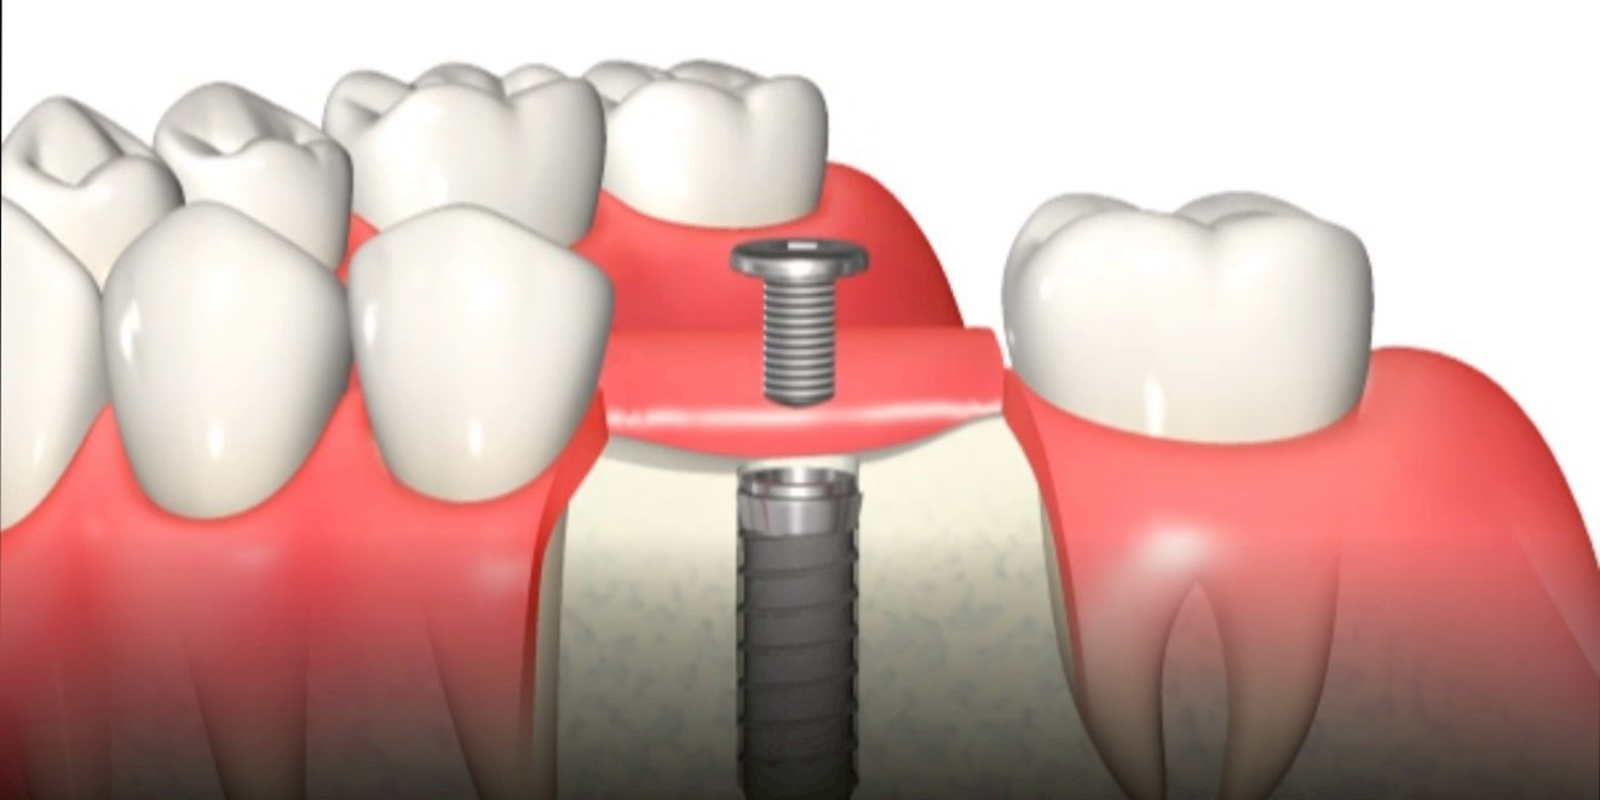

インプラント体(フィクスチャー)埋入窩の形成

事前にCTや模型にて計画していたインプラント埋入部位をラウンドバーにて、皮質骨に印記します。ニードルドリルを用いて、埋入位置を穿孔します。続いて、パイロットドリルを用いて埋入窩を拡大していきます。どこまで拡大するかは、患者様の骨の状態によります。形成した埋入窩に深度ゲージを入れて、対合関係や近遠心関係にズレがないか確認をします。ズレはその都度修正を行なっていきます。